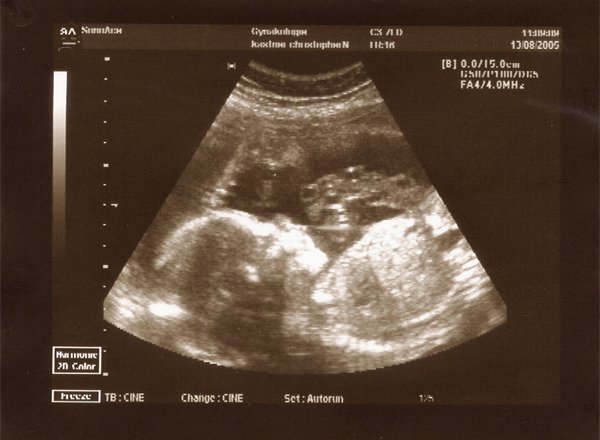

13.08.05 - 23. Woche - 25,8cm